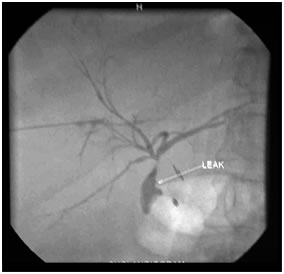

PTBD gram showing biliiary leak

PTBD gram showing type II biliary stricture